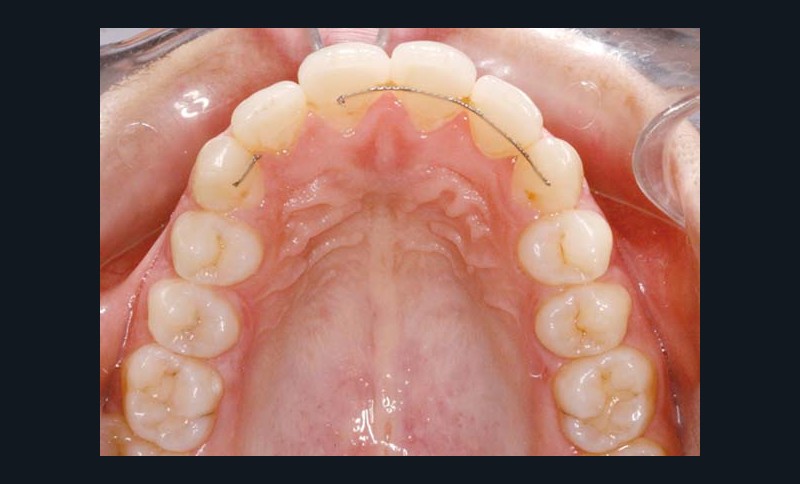

La patiente est appareillée en technique autoligaturante passive vestibulaire, Damon Clear (Ormco) au maxillaire et Damon Q (Ormco) à la mandibule avec sélection individualisée des torques selon les angulations radiculaires et des arcs .014 NiTi thermiques sont mis en place.